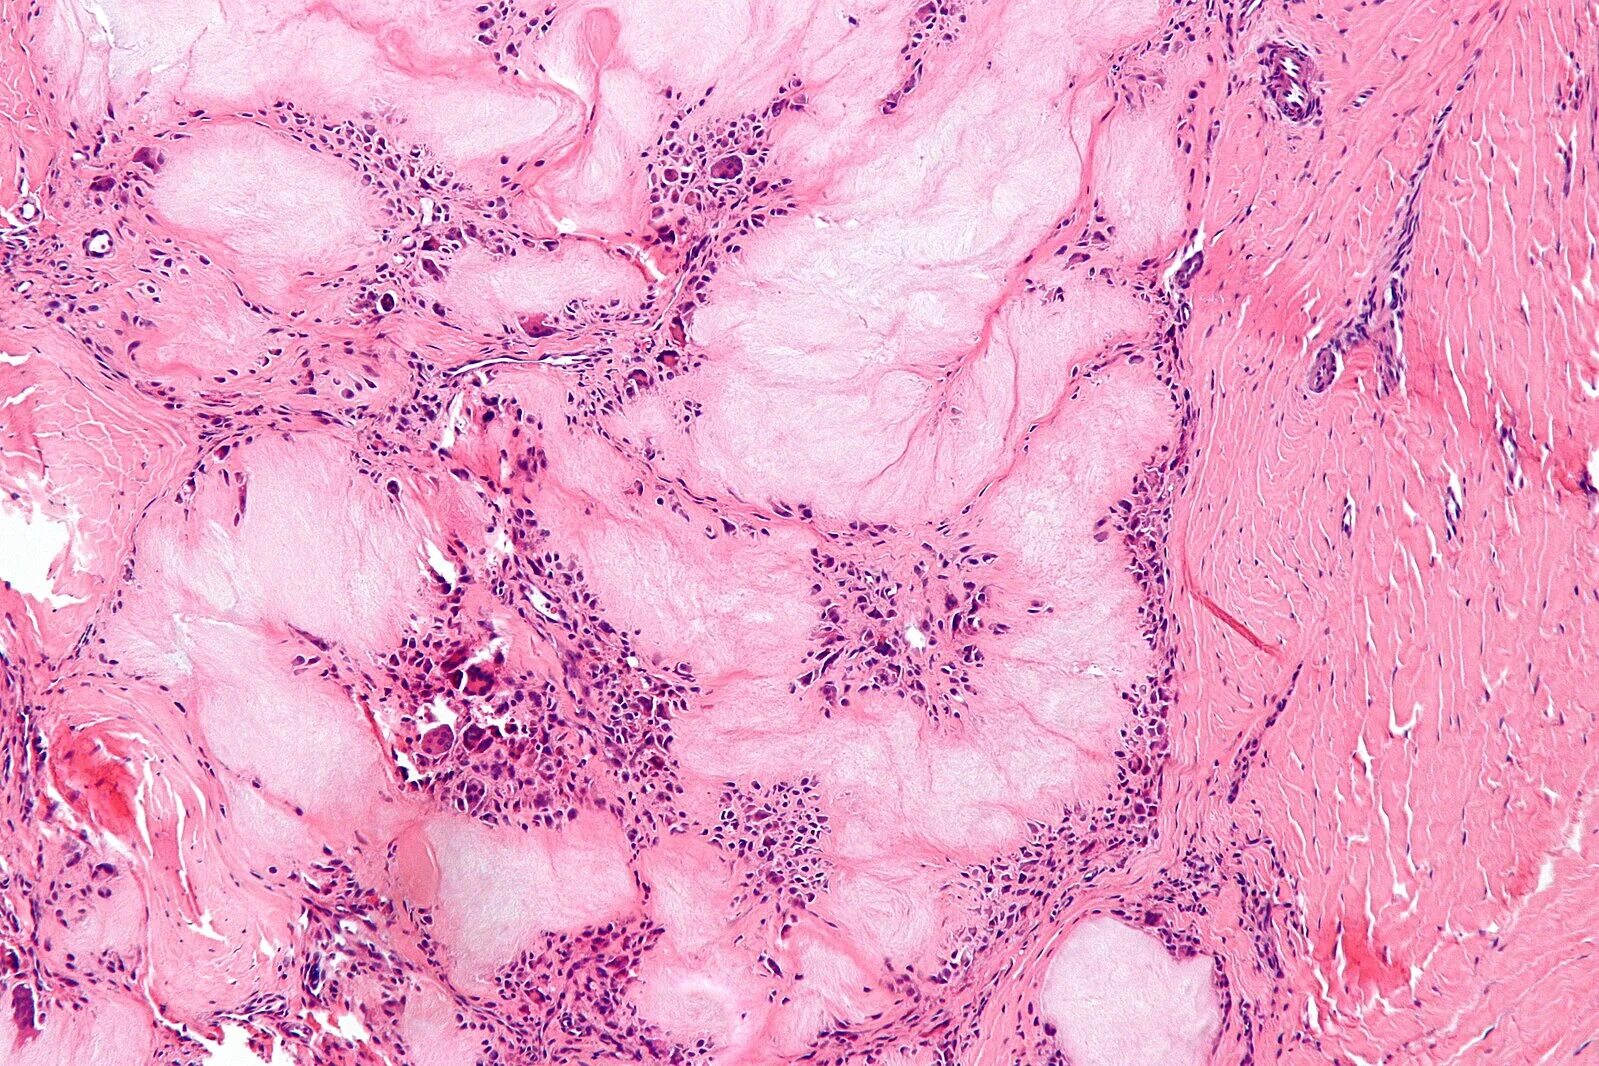

Патан пф